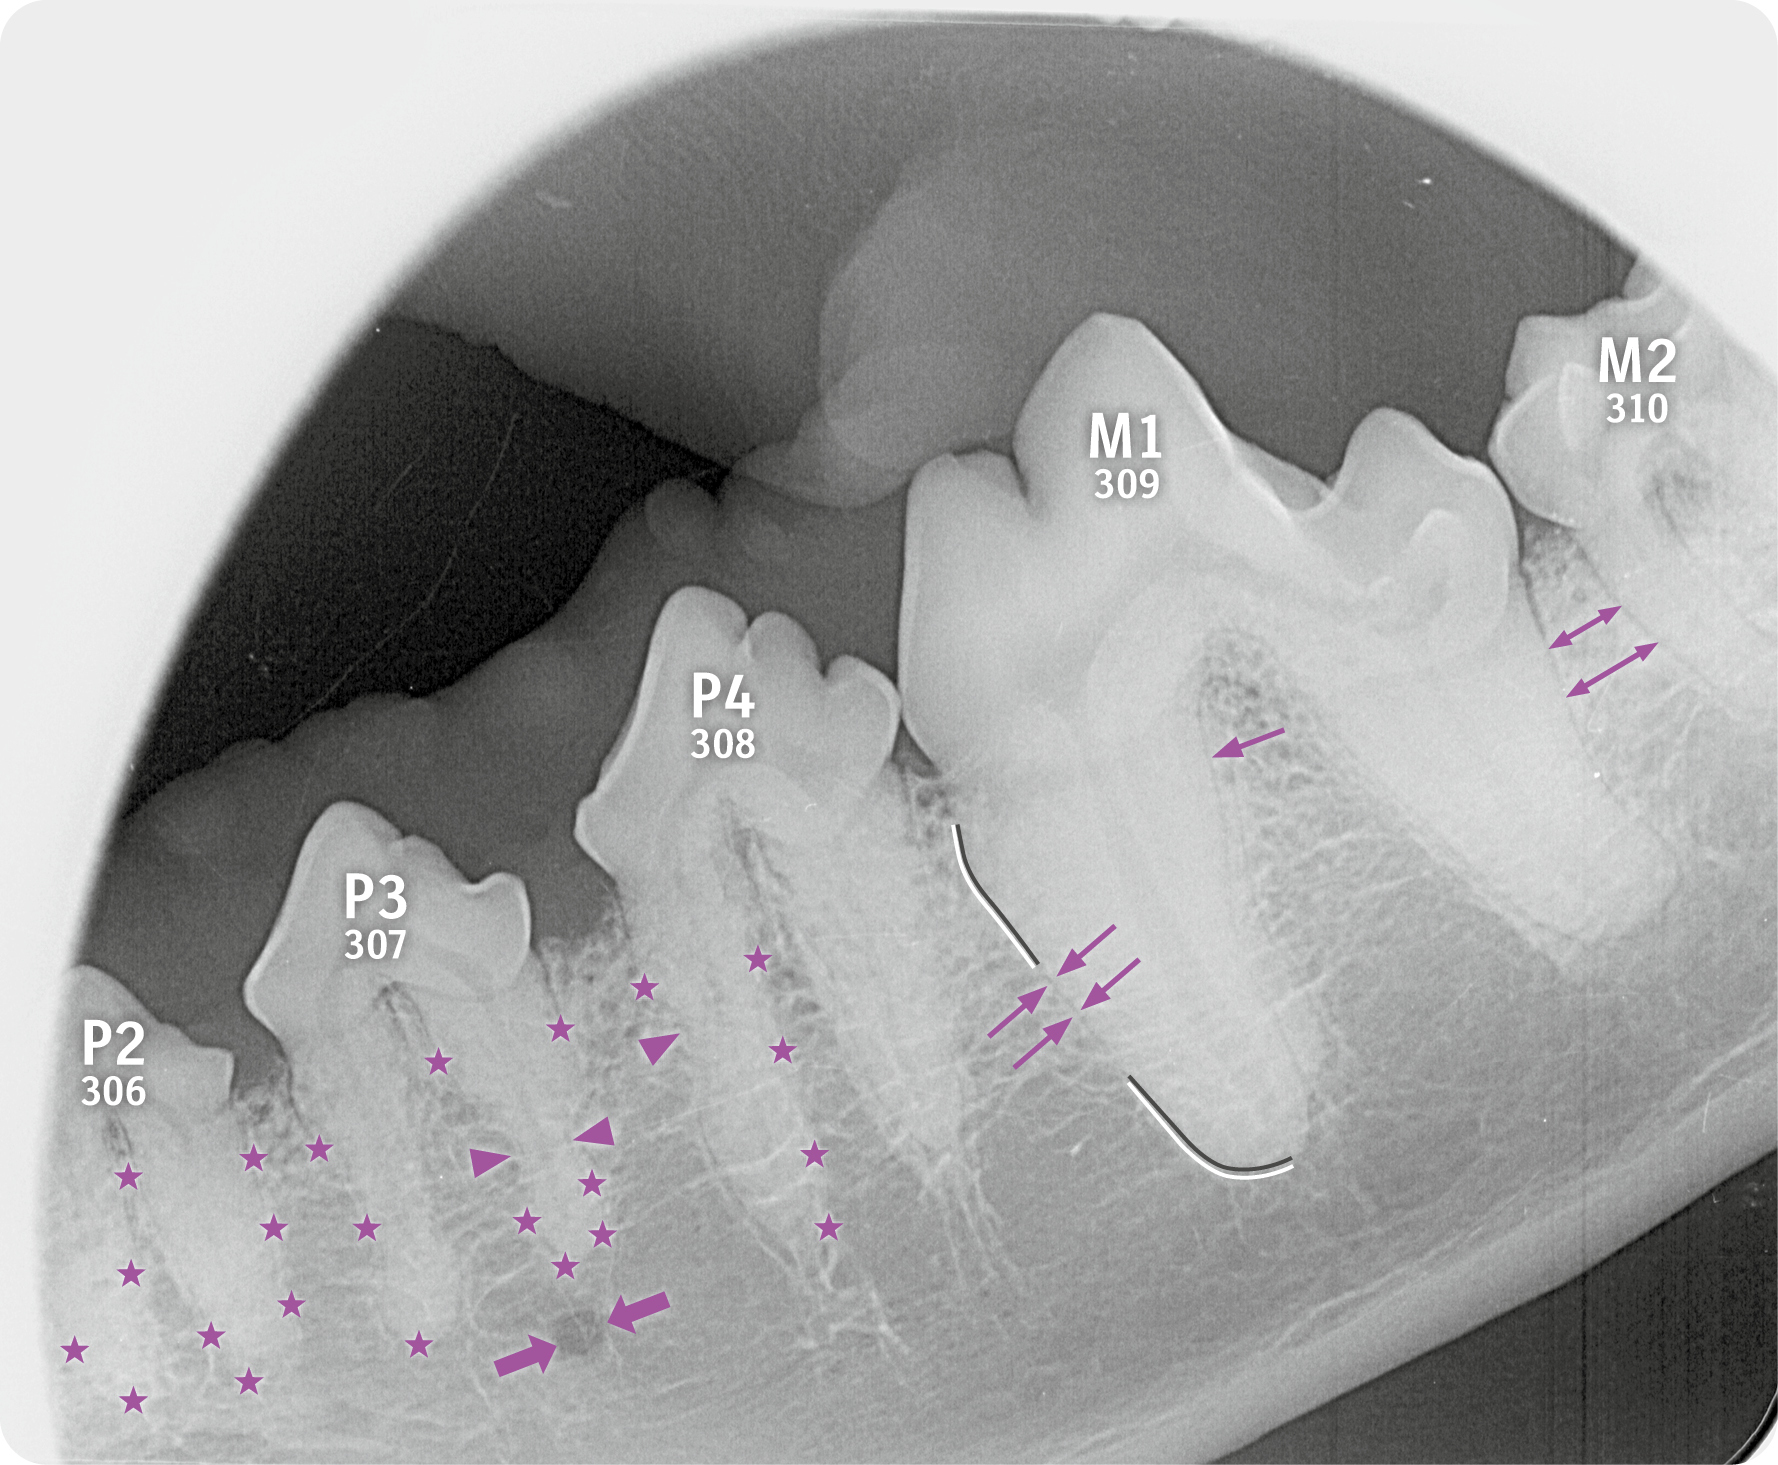

Auf dem Röntgenbild zeigt sich eine Aufhellung durch das Foramen mentale (dicke Pfeile), die normal ist. Wichtig zu wissen: Foramina mentalia können sich manchmal mit der Wurzel überlagern. Achten Sie darauf, das Foramen mentale nicht mit einer Zyste, einem Wurzelgranulom oder einer Osteolyse in Wurzelnähe zu verwechseln.

Eine Zahnresorption oder Tooth Resorption (TR) kommt sowohl bei Hunden (CORL) als auch bei Katzen (FORL) vor. Diese Dentalaufnahme eines Hundes zeigt eine normale Zahnwurzel, die von der Alveole (Lamina dura = weiße Linie) durch das peridontale Ligament (dunkler Saum = dunkle Linie) abgegrenzt ist (dünne Pfeile).

Ebenfalls auf dem Röntgenbild zu erkennen ist der Verlust des peridontalen Ligaments (Sternchen) sowie eine Reduktion der Röntgendichte der Zahnwurzel und eine Resorption der Wurzeln (Pfeilspitzen).